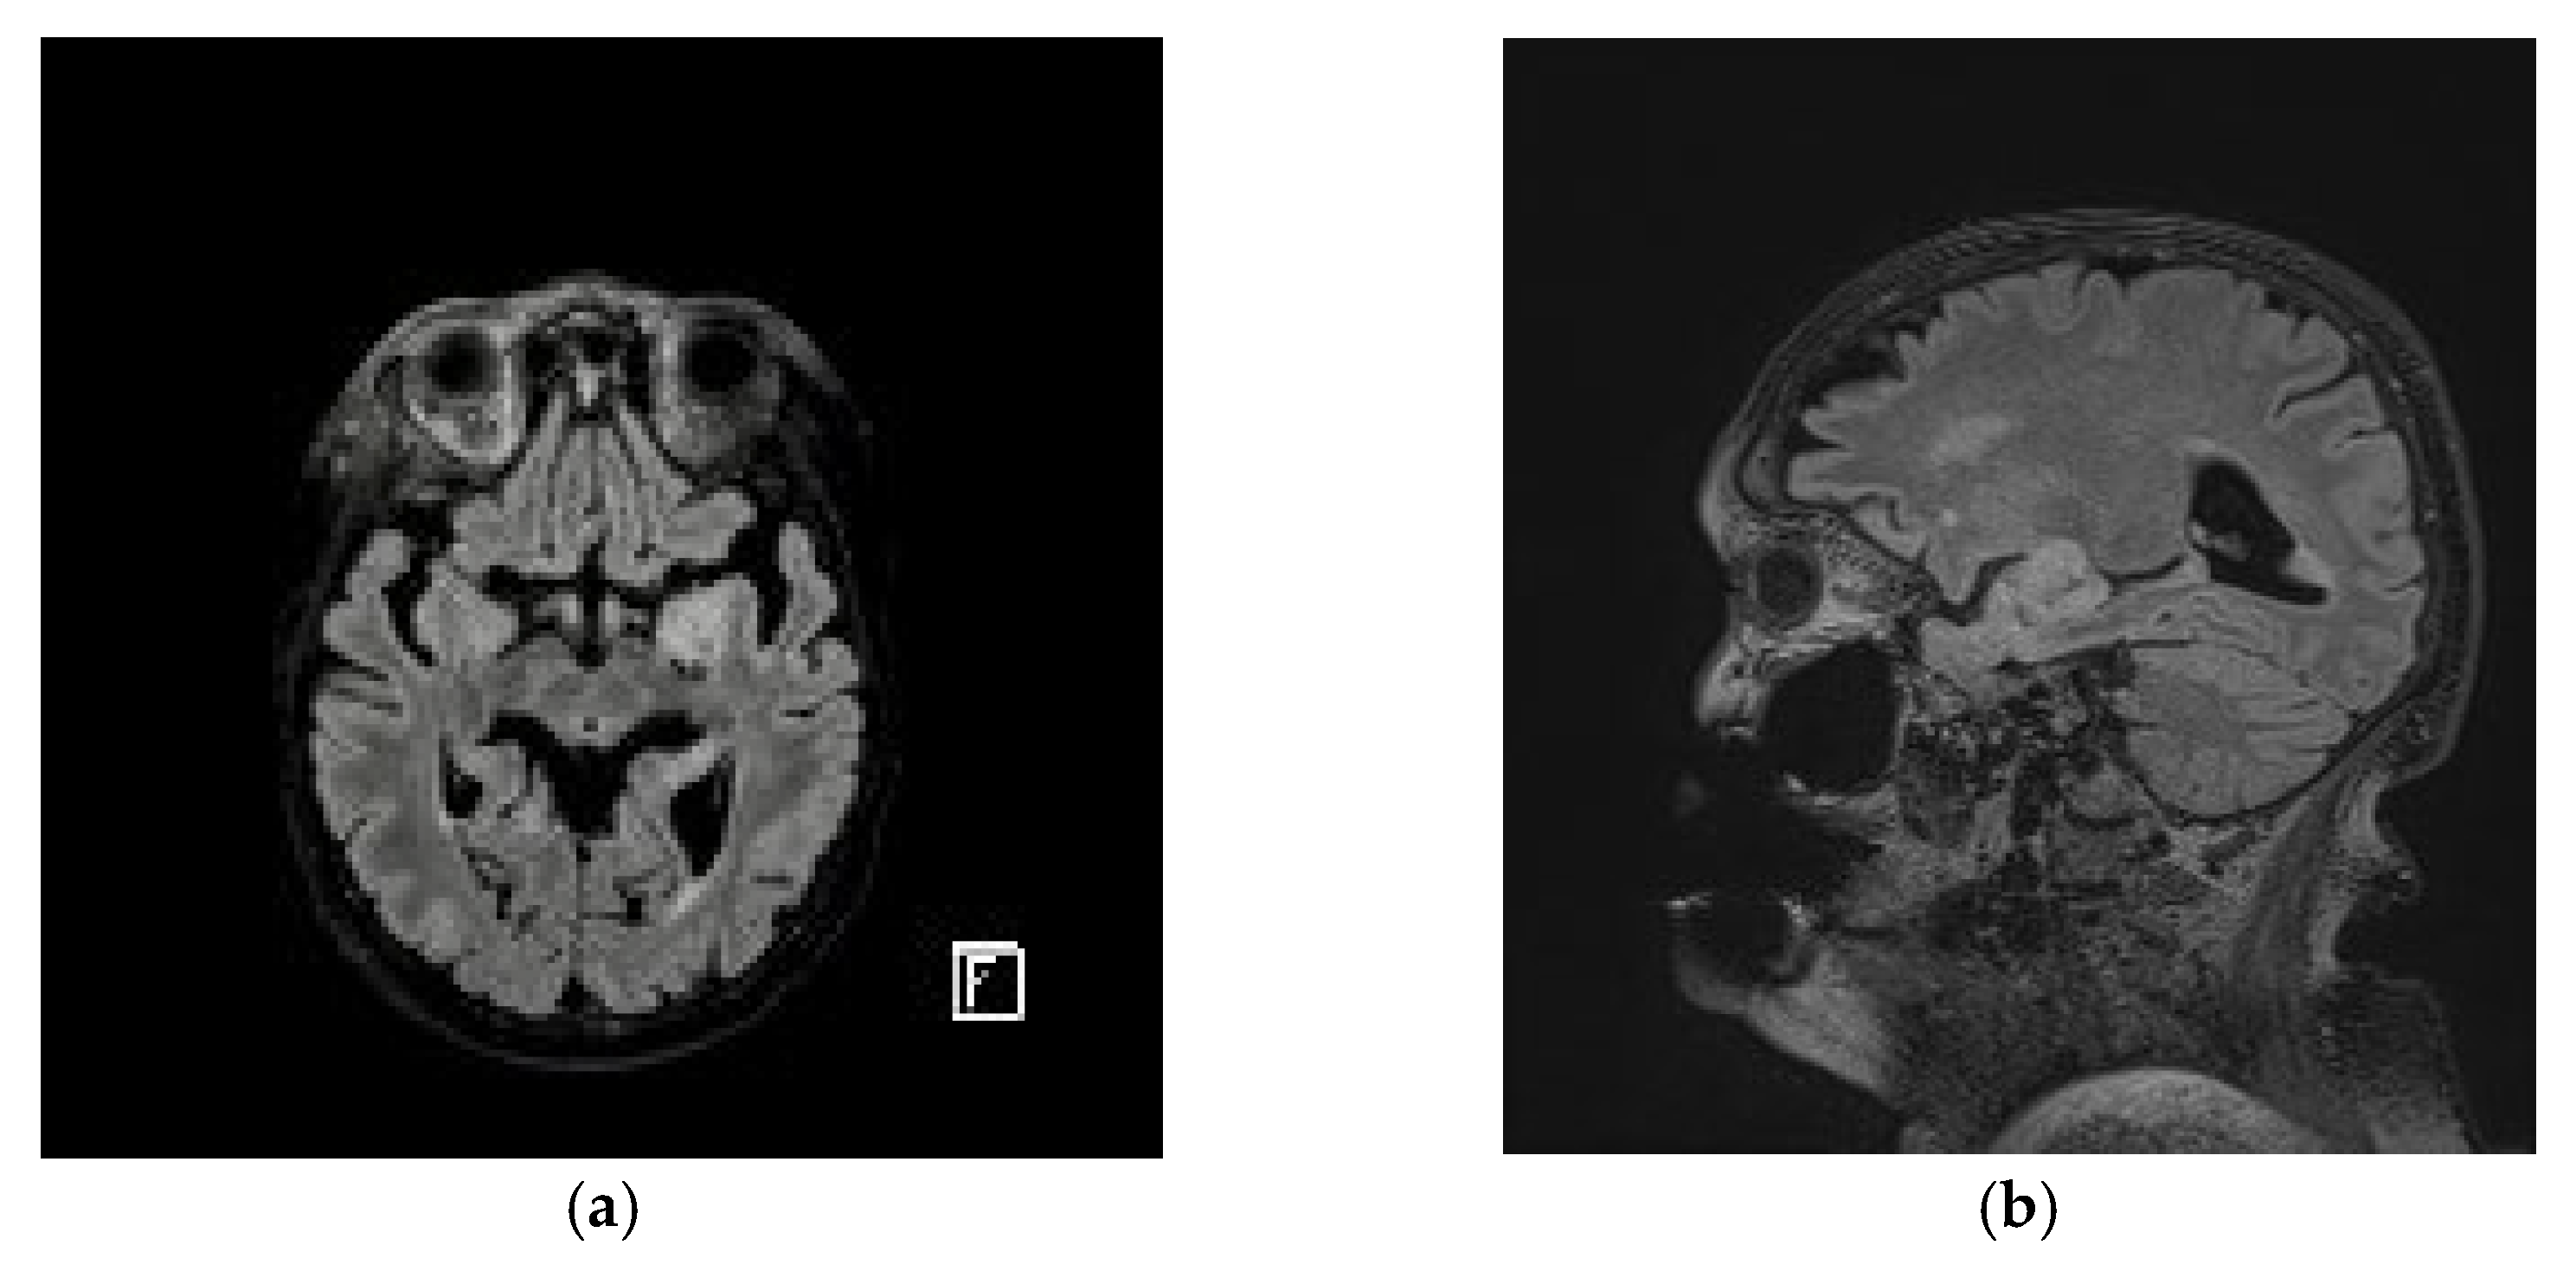

2. Case Presentation